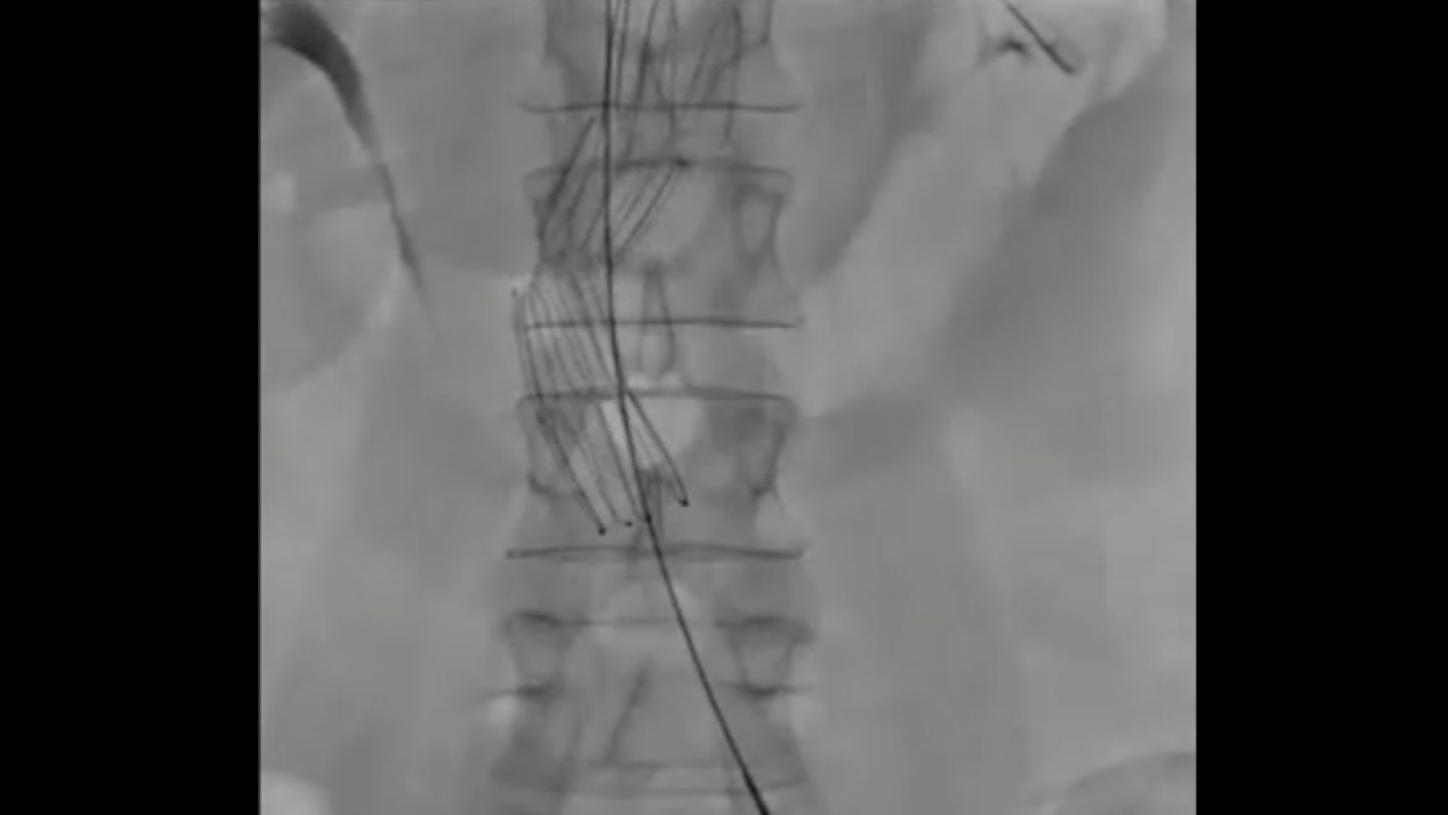

Iliosacral Screw Fixation, Spinal Fusion

syngo DynaCT Large Volume and syngo DynaCT 360 can visualize large anatomical areas

- Spine: Height of up to 23.5 cm (9.3”)

Clinical images courtesy of University Hospital Ulm, Germany (left) and Jikei University, Tokyo, Japan (right).